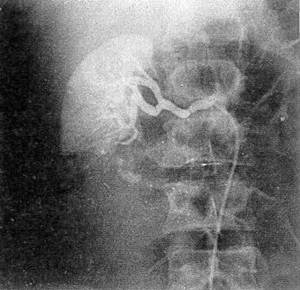

Уточнить тяжесть повреждения почки позволяет ангиография (рис. 34). Отношение к ангиографии неоднозначное. Одни клиницисты (М. К. Щербатенко и соавт., 1973; Л. С. Зингерман, Т. А. Ахадов, 1986) применяют аорто- и целиакографию для топической диагностики повреждений органов брюшной полости даже у пострадавших, госпитализированных с клиникой продолжающегося внутрибрюшного кровотечения, проводя одновременно противошоковую терапию; другие (и их большинство) — только при стабильных показателях гемодинамики для распознавания травмы почки, субкапсулярного разрыва селезенки, печени, причем у больных с клиникой гемобилии при обнаружении внутрипечёночной гематомы осуществляется эндоваскулярная эмболизация кровоточащего сосуда (В. С. Шапкин и соавт., 1987; Г. Н. Цыбуляк, 1985, 1995).

Р и с 34 Ангиограмма правой почки больного В , 32 лет ангиографическая картина отрыва нижнего полюса почки